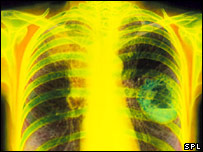

Pacientes com câncer no pulmão tiveram expectativa de vida aumentada depois de medicamento

Um medicamento para câncer de pulmão, ainda em fase experimental, prolongou a expectativa de vida dos pacientes em mais de 50% em testes preliminares.